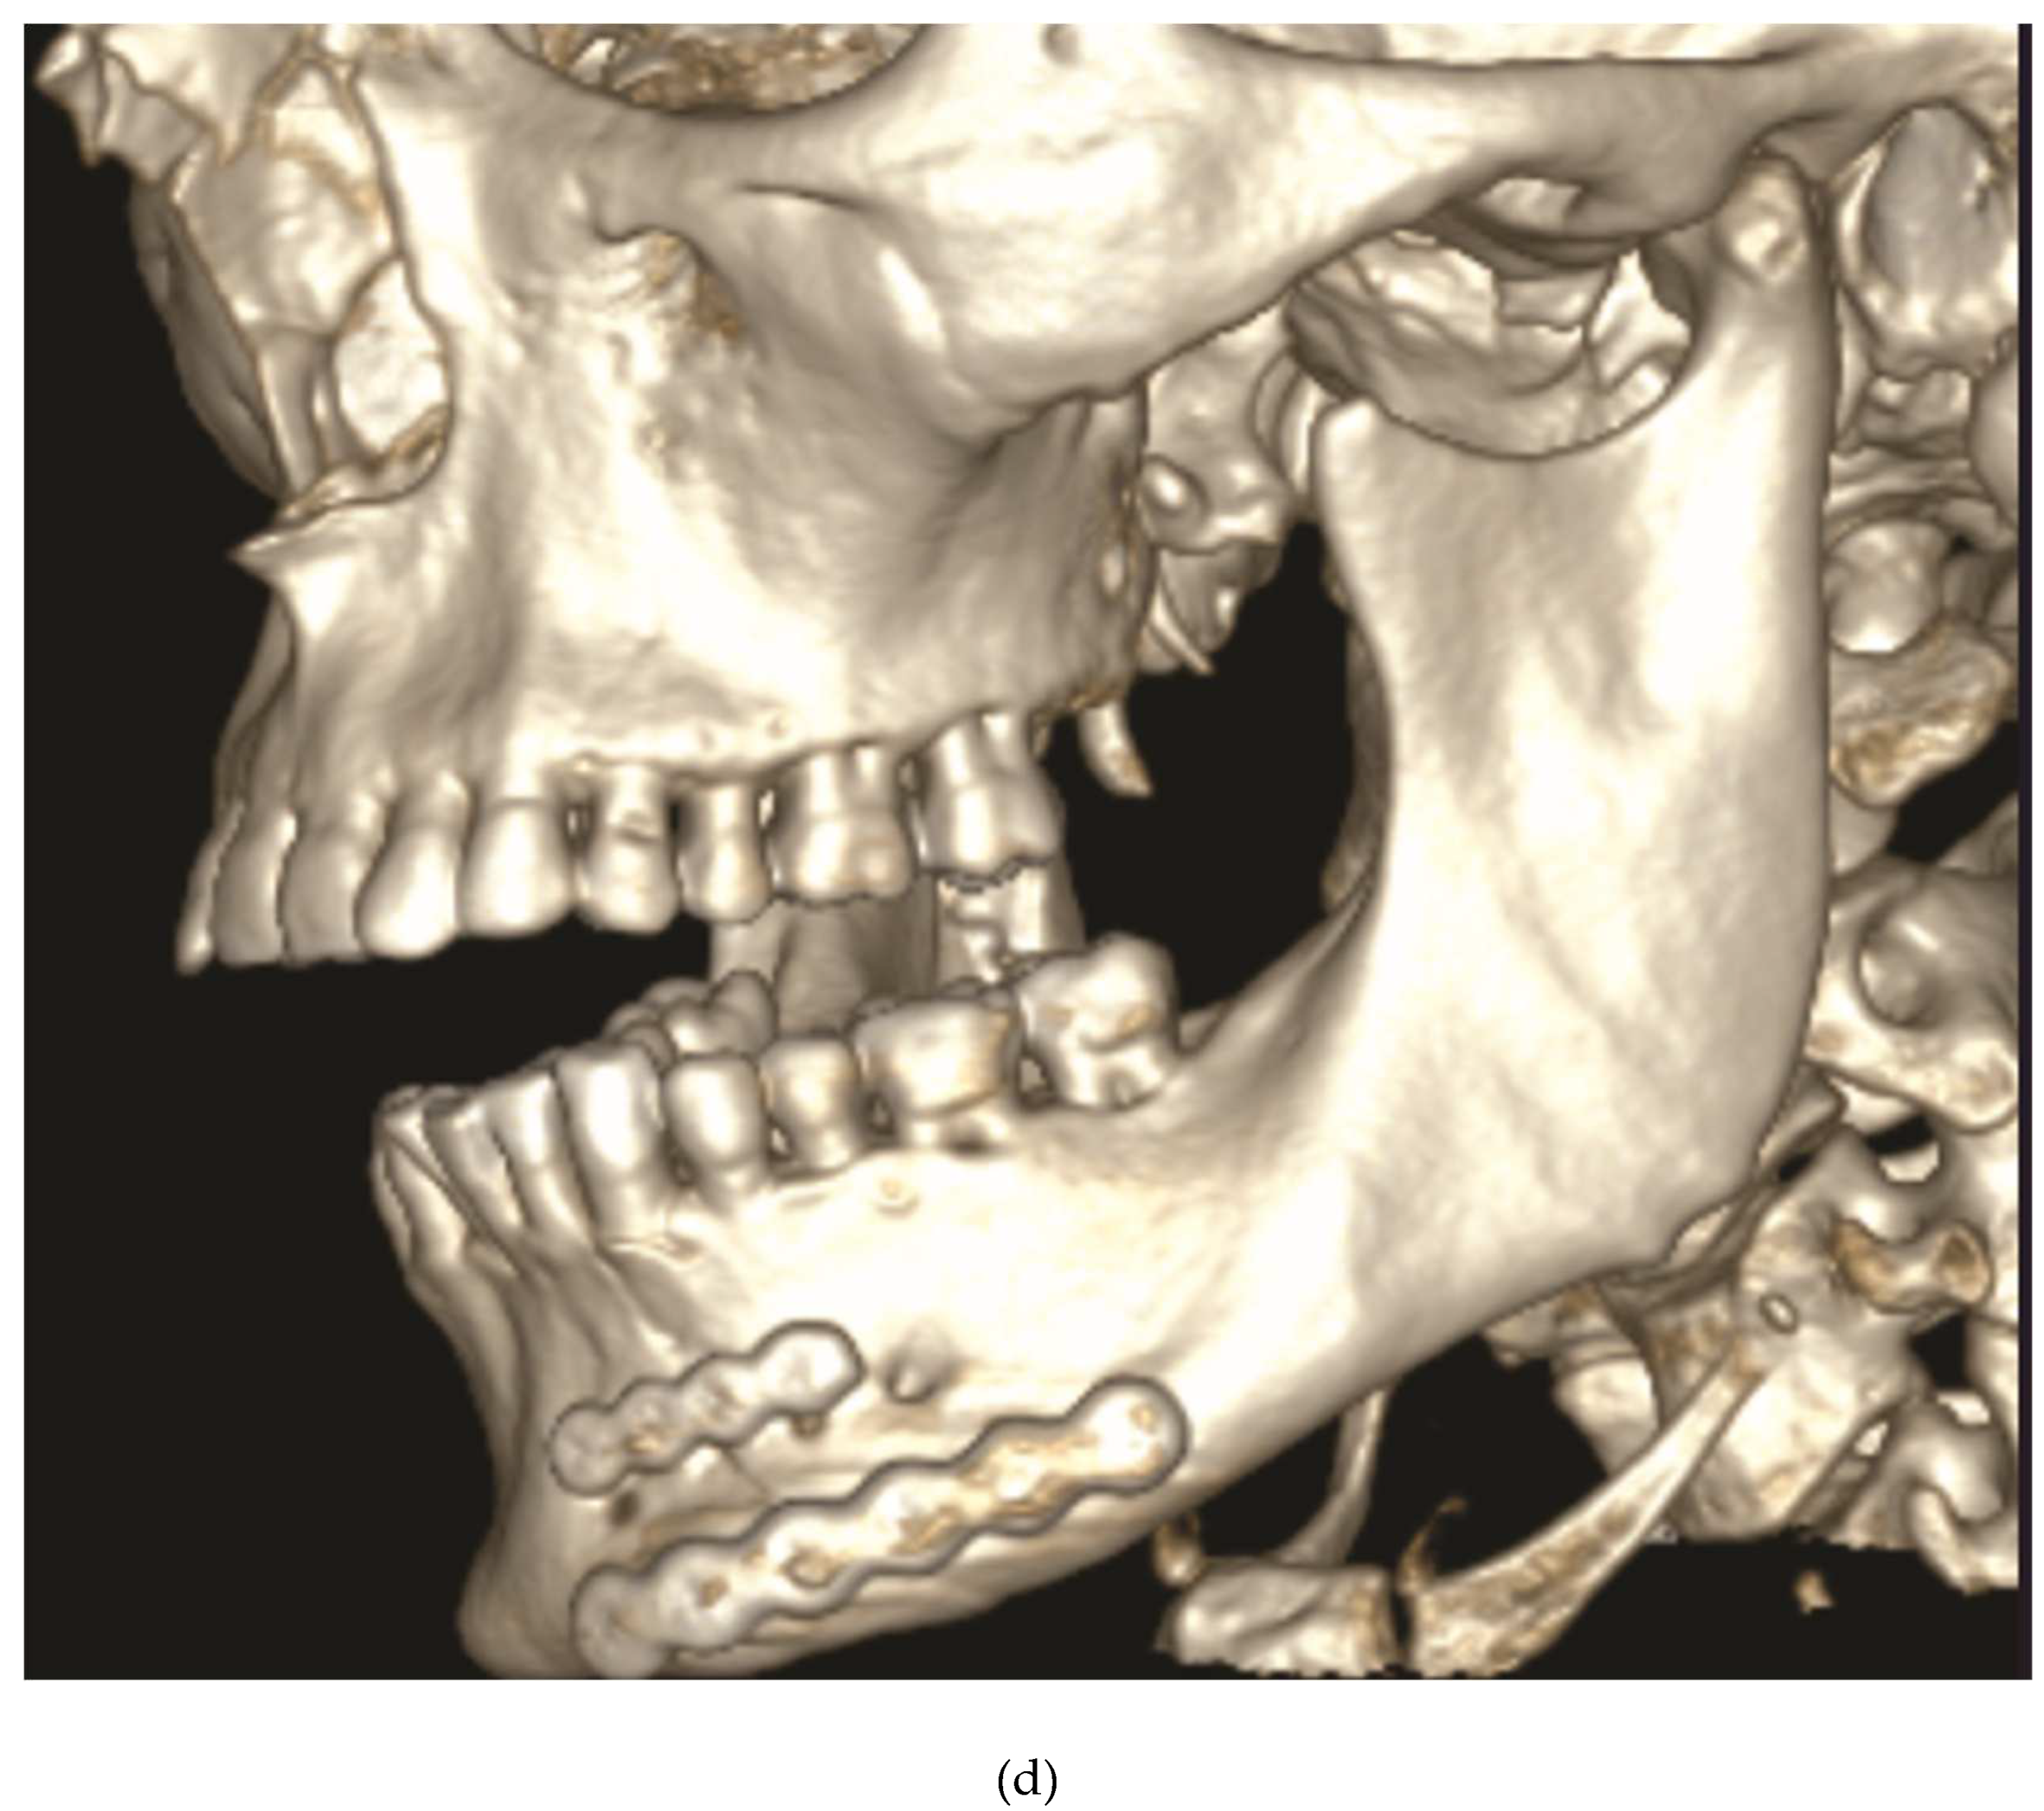

Figure 3.

Case Example – Neglected dentition unsuitable for circumdental wire fixation of arch bars in a self-inflicted gunshot injury. Use of an alternative to conventional arch bars: locking adaptation plates secured with self-tapping Locking bone screws into the alveolar rims, mounted with MMF nuts and interconnecting wire ligatures hooked over the protruding MMF nuts. Notice: bone fixation with screws inserted along mucogingival junction zones. Source/origin of Figure 3: Photograph collection – C.P. Cornelius